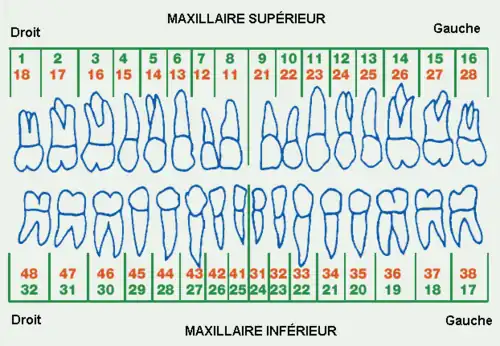

Le système de normalisation ISO de repérage des dents chez l'être humain, proposé par l'Organisation mondiale de la santé (OMS), est largement utilisé par les professionnels de la santé dentaire. Il est basé sur le système de notation utilisé par la Fédération dentaire internationale (FDI) et est connu sous le nom de ISO 3950[2].

Dans ce système, la dentition humaine est repéré selon quatre quadrants divisant les deux mâchoires. Dans chaque quadrant, les dents sont numérotés de 1 à 8.

Le quadrant est lui-même indiqué par un numéro de 1 à 8, selon sa position et selon le type de dentition décrit (provisoire alias « dents de lait » ou définitive alias « dents d'adulte »).

Le repérage « gauche » - « droite » fait référence à la position dans la bouche du patient mais correspond à la vision du dentiste ; la gauche et la droite sont donc inversées.

Dentition permanente

(« dents d'adulte »)

supérieure droite - 1 supérieure gauche - 2

18 17 16 15 14 13 12 11 | 21 22 23 24 25 26 27 28

DROITE --------------------------------------------------- GAUCHE

48 47 46 45 44 43 42 41 | 31 32 33 34 35 36 37 38

inférieure droite - 4 inférieure gauche - 3

Dentition temporaire

(« dents de lait »)

supérieure droite - 5 supérieure gauche - 6

55 54 53 52 51 | 61 62 63 64 65

DROITE --------------------------------- GAUCHE

85 84 83 82 81 | 71 72 73 74 75

inférieure droite - 8 inférieure gauche - 7

I - incisive

C - canine

P - prémolaire

M - molaire (dont dents de sagesse) |